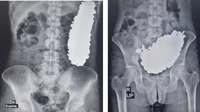

Salah satu contoh kasus dialami oleh seorang pria di Iran dan dipublikasikan di Journal of Medical Case Reports. Pasien berusia 36 tahun, datang ke RS dengan nyeri perut kronis, sering muntah, serta intoleransi terhadap cairan dan makanan. Dokter menemukan 452 benda logam di perutnya, seperti kunci hingga mur. (Foto: Journal of Medical Case Report).